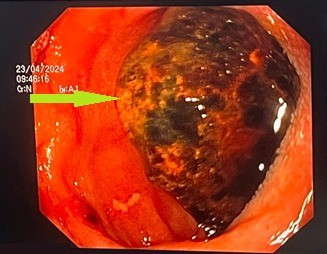

Thông qua hình ảnh chụp cắt lớp vi tính ổ bụng và nội soi tiêu hóa, các bác sĩ chẩn đoán bệnh nhân bị tắc tá tràng do sỏi mật (Hội chứng BOUVERET) kích thước rất lớn 3x5cm rò từ túi mật vào trong lòng tá tràng.

Bệnh nhân đã được nội soi tán nhỏ sỏi bằng laser, sau đó phẫu thuật mở ống tiêu hóa lấy viên sỏi ra ngoài, phục hồi lưu thông ống tiêu hóa. Sau 3 tuần điều trị, tình trạng bệnh nhân ổn định, ăn uống tốt và được xuất viện.